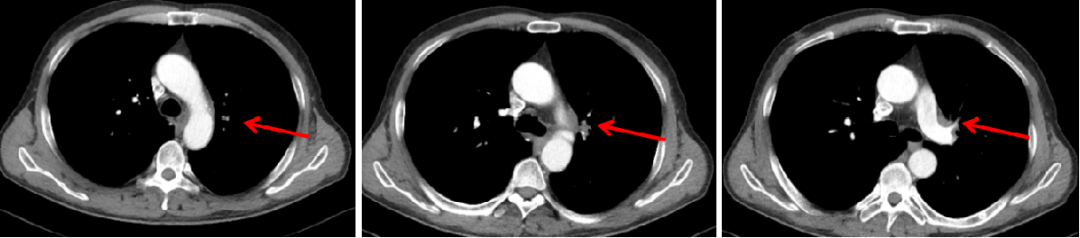

胸部CT(2020-03-03):左肺靶病灶直径59 mm,纵隔3、7区及双侧肺门淋巴结病灶直径20 mm(图1)。

图1:2020年6月7日,治疗前PET-CT

图2:2020年7月24日,联合治疗2周期后胸部CT

本例患者为左肺中心性鳞癌(cT4N3M1c,IVb期),伴多发淋巴结转移、左肺转移。经替雷利珠单抗联合化疗治疗,2个周期后左肺病灶和多发淋巴结转移病灶直径均明显缩小,疗效评价达到PR。患者目前已联合用药4周期,疗效持续PR,PFS近3个月,病情平稳,治疗过程中未出现明显消化道反应及骨髓抑制,安全性良好。